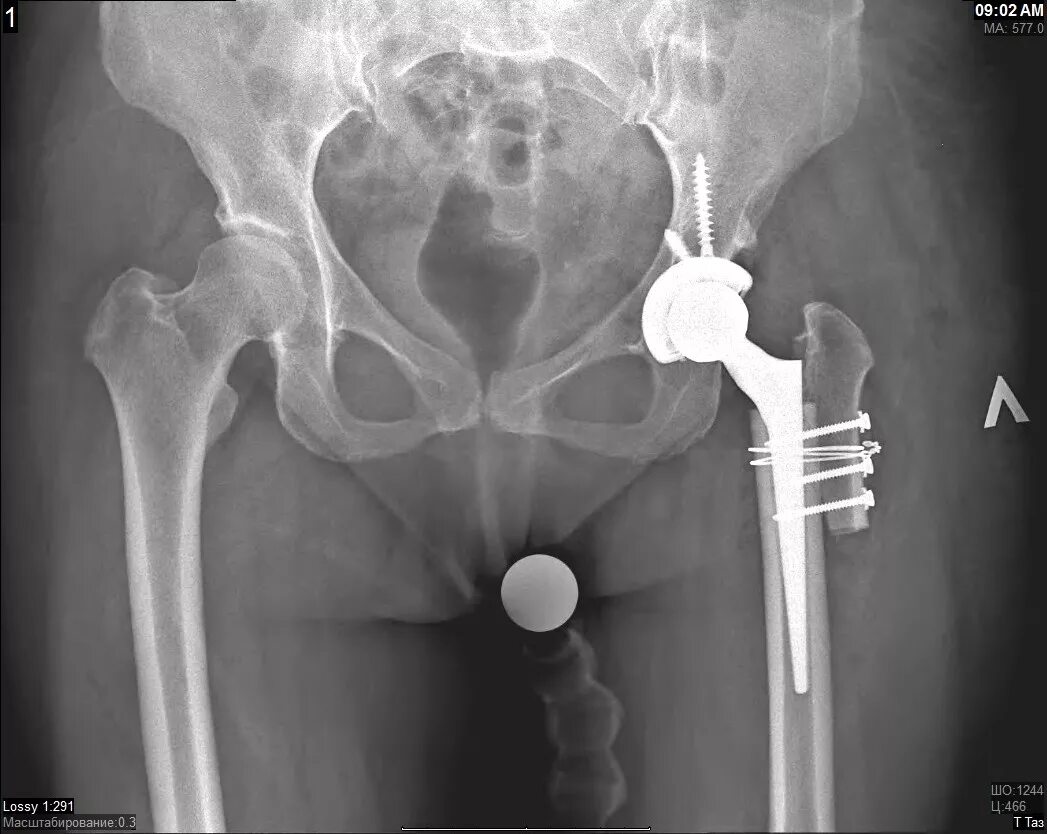

Эндопротез тазобедренного сустава москве